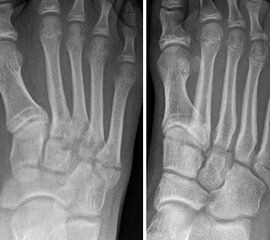

Lawrence und Botte Zone III

Weitestgehende Einigkeit besteht bei der OP-Indikation für metadiaphysäre Frakturen (Lawrence und Botte Zone III, Abb. 5) 20721. Exemplarisch sei hier die Studie von Mologne und Kollegen 21 genannt. Im Rahmen einer randomisierten kontrollierten Studie wurde eine restriktive konservative Behandlung (Entlastung und Gips, n=18) gegen eine operative Therapie (Schraubenosteosynthese, n=19) verglichen (Follow-up: 25 Monate). Dabei zeigte sich eine deutliche Überlegenheit der operativen Behandlung.

Stressfrakturen der MT V Basis werden häufig als eigene Entität beschrieben (Abb. 6). Allerdings kommen diese Frakturen hauptsächlich in der Zone III nach Lawrence und Botte vor (Khan, 2006). Eine systematische Literaturarbeit von Mallee und Kollegen 14 verglich die konservative und operative Therapie bei Patienten mit Stressfrakturen der MT V Basis. Basierend auf den Ergebnissen von 8 Studien konnten die Autoren auch hier eine Überlegenheit der operativen Therapie zeigen.